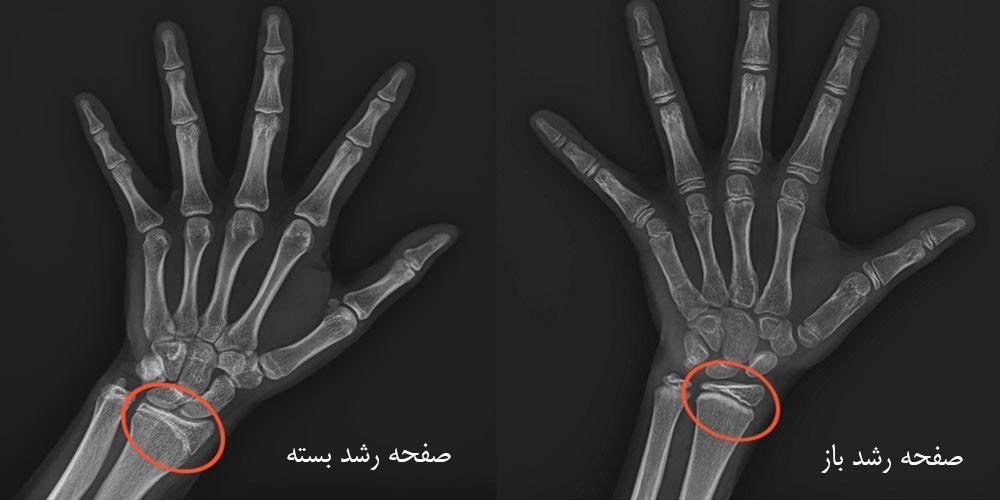

شکستگی صفحه رشد در کودکان

در نوجوانان که صفحه رشد فعال دارند، شکستگی‌های مچ دست می‌تواند صفحه رشد را درگیر کند. اگر شکستگی جابجایی خفیف داشته باشد، جااندازی بسته و گچ‌گیری کافی است. اما در موارد جابجایی شدید یا آسیب به سطح مفصلی، جراحی با پین برای پیشگیری از اختلال رشد آینده ضرورت دارد.